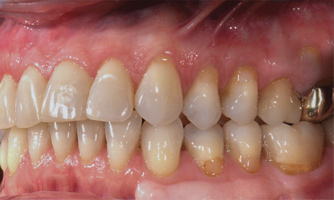

(23. AND 24.) Virtual restoration design and conventional surgical guide illustrating rudimentary entry points that do not allow control of drilling angulation and depth.

Figure 23

Figure 24